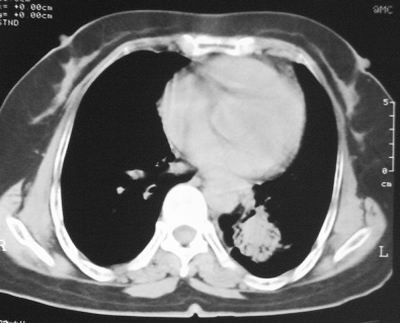

患者,女,64岁,4年前左腮腺"多形性"腺瘤手术治疗史.现复查胸部ct见左下肺块状影,该影与原左腮腺手术是否有联系?

本次复查胸部ct

左下肺软组织块影,有分叶、毛刺、空泡及胸膜牵拉征,左下肺周围性肺癌。

左肺下叶周围型肺癌,支持!(软组织肿块+分叶+毛刺+空泡+胸膜凹陷征)

左下肺后基底段实性肿块,周围有毛刺,病变周围有肺气肿,与降主动脉间有条带状影相连,病灶4年前查体发现,纵隔内未见肿大淋巴结。考虑.肺隔离症,建议增强扫描与周围型肺癌鉴别。